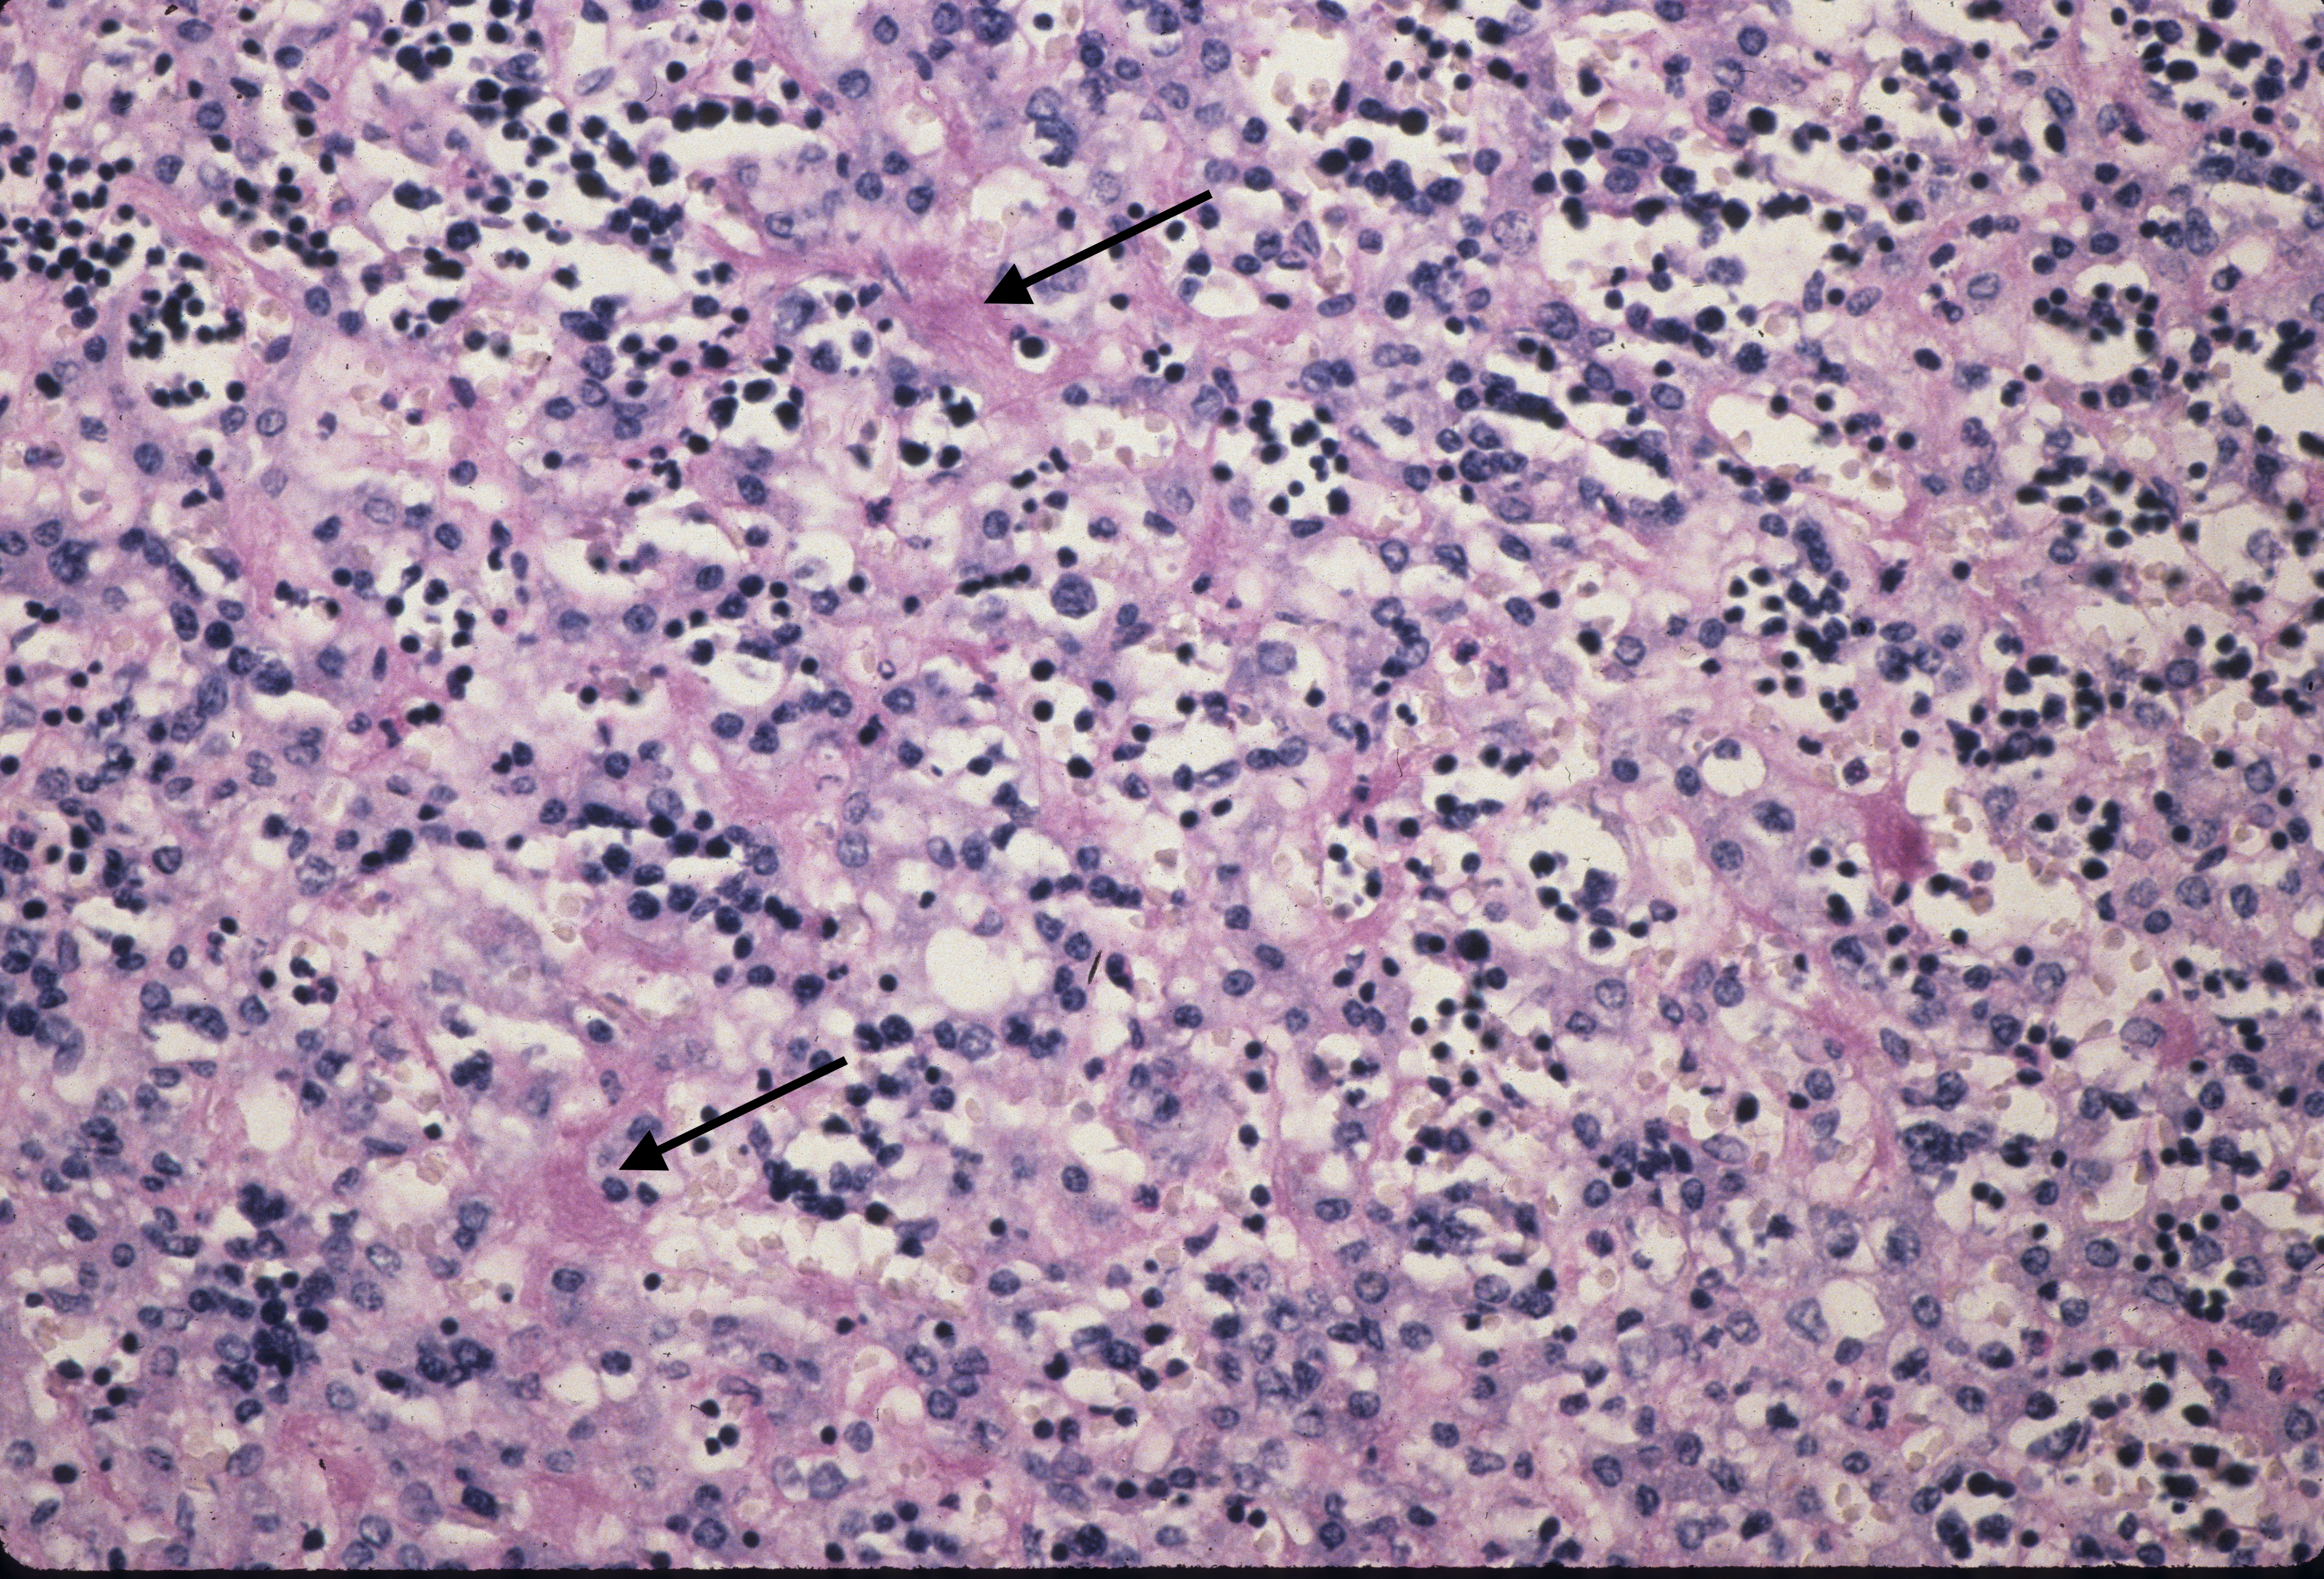

Hematopoiesis: The liver is a major site of fetal hematopoiesis. Erythropoiesis and megakaryocytopoiesis occur in the liver sinusoids. Erythropoiesis is increased with conditions requiring increased production such as fetal hemolysis or hemorrhage, and in macrosomic infants of diabetic mothers2. The extent of erythropoiesis decreases with gestational age (Fig 4a, b).

With pathologically increased erythropoiesis there is often grouping of cells at the same stage in erythropoietic development (fig 5a, b).